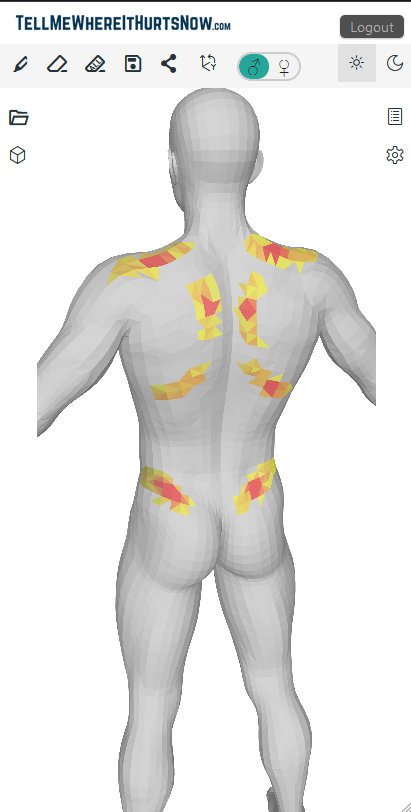

TellMeWhereItHurtsNow: Web app for visual pain communication. Mark areas on 3D body model, show intensity, share with doctors. Track pain over time. Works on all devices. Show doctors exactly where it hurts to improve communication and understanding.